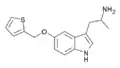

α-Alkyltryptamines are a group of substituted tryptamines which possess an alkyl group, such as a methyl or ethyl group, attached at the alpha carbon, and in most cases no substitution on the amine nitrogen.[17][18][19] α-Alkylation of tryptamine makes it much more metabolically stable and resistant to degradation by monoamine oxidase, resulting in increased potency and greatly lengthened half-life.[19] This is analogous to α-methylation of phenethylamine into amphetamine.[19]

Many α-alkyltryptamines are drugs, acting as monoamine releasing agents, non-selective serotonin receptor agonists, and/or monoamine oxidase inhibitors,[20][21][22][23] and produce psychostimulant, entactogen, and/or psychedelic effects.[17][18][19] The most well-known of these agents are α-methyltryptamine (αMT) and α-ethyltryptamine (αET), both of which were used clinically as antidepressants for a brief period of time in the past and are abused as recreational drugs.[18][19] In accordance with its action as a dual releasing agent of serotonin and dopamine, αET has been found to produce serotonergic neurotoxicity similarly to amphetamines like MDMA and PCA, and the same is also likely to hold true for other serotonin and dopamine-releasing α-alkyltryptamines such as αMT, 5-MeO-αMT, and various others.[24]

BW-723C86 | 1-[5-(2-Thienylmethoxy)-1H-indol-3-yl]-2-propanamine | 160521-72-2 |